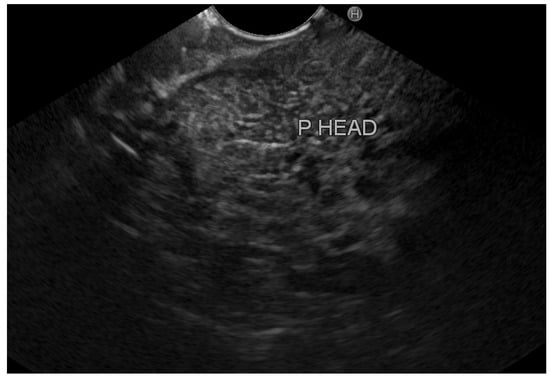

Overall, we identified eight patients with inflamed tissue on EUS (group A) vs. 42 patients with normal pancreatic tissue (group B). Figure 2 demonstrates an EUS image with inflamed pancreatic head tissue (heterogeneous echo pattern, decreased echogenicity with edema), and Figure 3 demonstrates normal pancreatic head parenchyma. All patients in group A had clinically mild acute pancreatitis. However, in group B, 33 patients (78.6%) had mild disease, 7 patients (16.7%) had moderate disease, and 2 patients (4.8%) had severe disease. Exploring the optimal timing for performing EUS, we found that among patients with normal pancreatic tissue, the average period until performing EUS from hospital discharge was 44.7 ± 28.3 days (20–120); among patients with inflamed pancreatic tissue, EUS was performed 48.1 ± 22.3 days (20–90) from discharge. Table 2 demonstrates the characteristics of patients with inflamed and normal pancreatic tissue on EUS.

Figure 2. Inflamed pancreatic parenchyma. P HEAD: pancreatic head.

Figure 3. Normal pancreatic parenchyma. CBD: common bile duct; PC: portal confluence; P HEAD: pancreatic head.